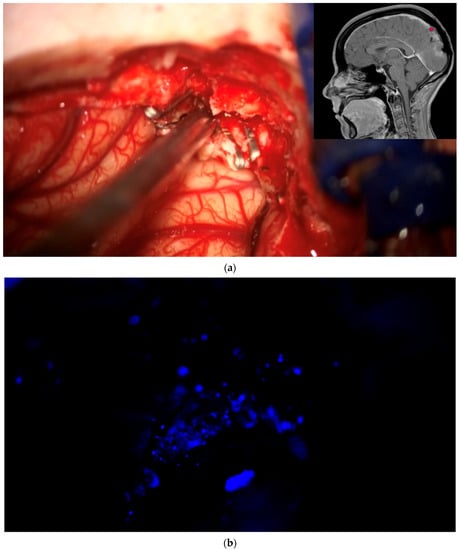

During the course of conventional white light surgery, the surgeon might encounter tissue which appears uncertain. From such “indeterminate” tissue the surgeon might require more information based on fluorescence. In such cases, the observation of fluorescence might lead to a change in surgical decision or surgical strategy. Such instances of indeterminate tissue may be found at the dural tail, in scar tissue with cases of recurrent meningioma, in the bone flap or at bony resection margins. In cases in which the surgeon requires more information based on fluorescence, the region in question is marked by the navigation pointer and a screenshot is taken. At this stage, the surgeon records his presumed diagnosis for the tissue area he or she desires more information for (“likely” or “unlikely” tumor) and his surgical decision based on his impression under white light (to resect or not to resect). The surgeon then switches to blue light, records whether he or she sees fluorescence, and states whether he or she plans to change surgical strategy based on fluorescence status. Under white light, the uncertain tissue is then biopsied for later histological evaluation. The entire process is recorded using the microscope’s video camera for later assessment by the review panel (Figure 2).

Biopsy from “indeterminate” tissue: In this study the surgeon might encounter tissue which appears uncertain (tumor or not, “indeterminate” tissue) during surgery and where fluorescence might be helpful. The location of a respective region is documented by the neuronavigation screenshot. The illumination is changed to blue light to determine whether the tissue fluoresces and a biopsy is then taken. The tissue interrogation procedure is recorded by video. (a) In this example a portion of the sagittal sinus infiltrated by meningioma has been resected. The anterior resection margin appears inconclusive as to whether it still contains tumor and is therefore regarded as being indeterminate. The location is documented using neuronavigation. The insert shows the pointer tip location marking the intended biopsy location. (b) No fluorescence is observed. The location is then biopsied. (c) Neuronavigation screenshot “A”: anterior; “P”: posterior; “L”: left; “R”: right).